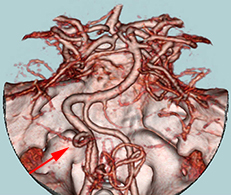

<画像所見>

左後下小脳動脈が左舌咽神経を圧迫していたために左咽頭部を中心に激しい痛みが生じていた。

左後下小脳動脈(矢印)は術後に本来の位置から移動している。